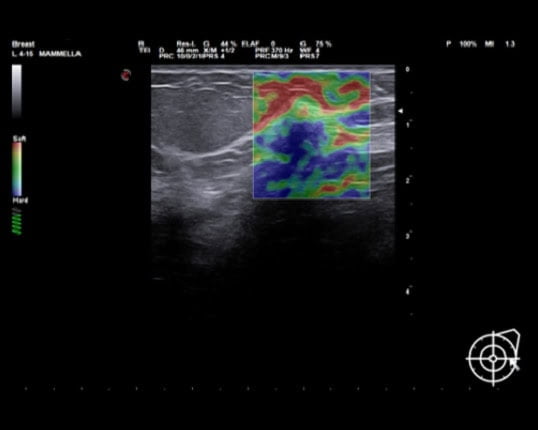

ElaXto – Siêu âm đàn hồi mô định tính: Xác định độ đàn hồi mô cùng tỷ lệ độ cứng, tỷ lệ đường kính E/B ứng dụng trong vú, giáp, cơ xương khớp và được hướng dẫn bởi hiệp hội siêu âm thế giới WFUMB.

may sieu am mylab x7